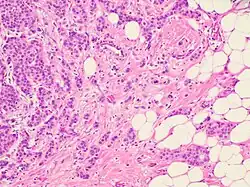

Despite the structural diversity of the primary breast tumor, five main types of morphological structures can be distinguished: alveolar, trabecular, tubular and solid structures, and discrete groups of tumor cells. The alveolar structures are tumor cell clusters of round or slightly irregular shape. The morphology of the cells that form this type of structures varies from small cells with moderate cytoplasm and round nuclei to large cells with hyperchromatic nuclei of irregular shape and moderate cytoplasm. The trabecular structures are either short, linear associations formed by a single row of small, rather monomorphic cells or wide cell clusters consisting of two rows of medium-sized cells with moderate cytoplasm and round normochromic or hyperchromatic nuclei. The tubular structures are formed by a single or two rows of rather monomorphic cells with round normochromic nuclei. The solid structures are fields of various sizes and shapes, consisting of either small cells with moderate cytoplasm and monomorphic nuclei or large cells with abundant cytoplasm and polymorphic nuclei. Discrete groups of cells occur in the form of clusters of one to four cells with variable morphologies.[2]

The different morphological structures of breast tumors correspond to certain types of invasion. Therefore, alveolar, trabecular, and solid structures that are characterized by the presence of cell-cell contacts may be referred to morphological manifestations of collective migration, while discrete groups of tumor cells may be referred to manifestations of individual migration. The first batch of data obtained in a study of the expression of cell adhesion genes confirms this hypothesis. For example, there was a decrease in the activity of the genes of cadherins, which are responsible for cell-cell contacts, in the order: solid – alveolar and trabecular structures – discrete groups of tumor cells. In this case, the number of expressed genes of integrins involved in the adhesion of tumor cells to the extracellular matrix was reduced in the order: solid and alveolar – trabecular structures – discrete groups of tumor cells.[2]